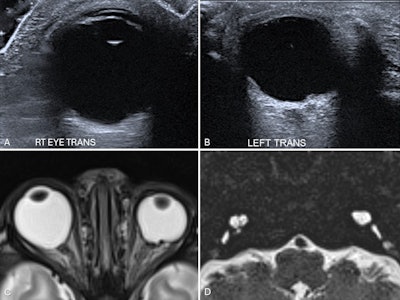

Bilateral coloboma in a 15-day-old neonate with CHARGE syndrome. Ultrasound images of the right eye (A) and left eye (B) show focal defects in the posterior globe with vitreous herniation, suggestive of bilateral colobomas. Axial T2-weighted MR image of the orbits (C) confirms the ultrasound findings. A heavily T2-weighted axial MR image of the petrous temporal bones (D) shows bilaterally dysplastic cochleae and vestibules, with absent semicircular canals -- findings consistent with CHARGE syndrome.